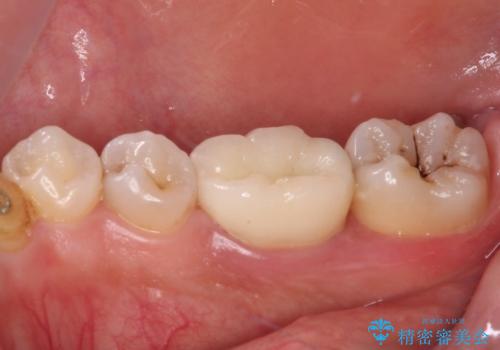

放置した虫歯 根管治療とオールセラミッククラウン

術前の診査では、神経を取り除かなくても済む可能性が示唆されましたが、実際に虫歯除去を進めたところ、レントゲン写真から読み取れる通り、神経組織にまで虫歯が及んでいることが分かりました。

速やかにラバーダム下にて根管治療を行うこととし、その後オールセラミッククラウンにて補綴治療を行うこととしました。

治療期間中、痛みが生じることはなく、処置後3か月経過しましたが良好な状態を保っています。